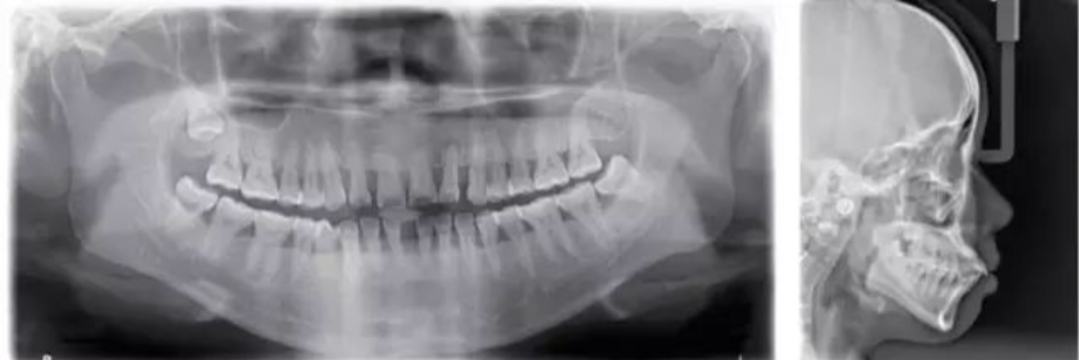

这两张是做正畸治疗的必备X光片,分别是全景牙片和头颅侧位片。医生接诊后,会把这个定为初诊病例,经与患者交流沟通确定需要做正畸治疗后,最重要的就是拍这两张X光片检查,这是患者与医生定方案的重要信息。这是第一步。